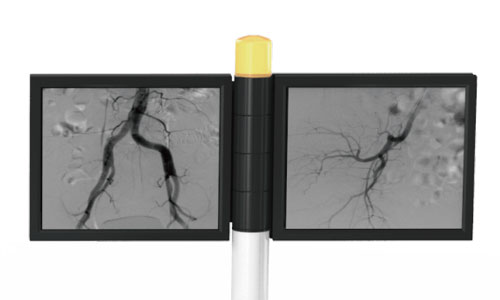

Large dynamic FPD with smaller pixel size, ensuring distortionless imaging; Wider FOV, avoiding overlapping and omissions, reducing exposure time and radiation dose, and shortening the operation time.

Large dynamic FPD

More than doubled imaging area

Meeting the surgical needs of about 80% large DSA equipment